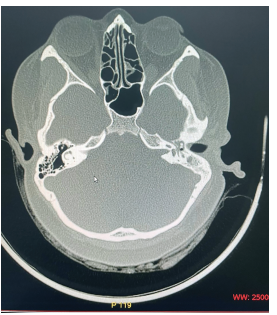

Introduction: Heterotopic Brain and Encephaloceles of middle ear usually present with symptoms of ear discharge and hearing loss. Some patients have additional symptoms of headache, abnormal ringing sensation and vertigo. Radiology may or may not show a communication with central nervous system in encephaloceles and the bony defect may be unnoticeable or attributed to the thinning of bone due to chronic otitis media. On computerised tomography, no distinction may be made between fluid, granulations, cholesteatoma and other space occupying lesions. Morphologically, it may be identified grossly if it presents with its characteristic pink colour and typical convoluted cerebriform pattern (CCP).  Methods: A 26 years female presented to us with unilateral ear discharge since birth and unilateral hearing loss on ipsilateral side for last 18 months. Clinically, radiologically and morphologically it mimicked chronic otitis media with cholesteatoma with no pre-operative and intra-operative distinction from the later. However, the coronal section at the level of anterior tegmen showed a small defect of the tegmen. T2 weighted MRI confirmed presence of brain tissue in middle ear and mastoid cavity. Results: Combined Middle Cranial Fossa and mastoid approach were employed, unviable brain tissue was excised and sent for histopathology. Viable brain tissue was reduced and tegmen defect was closed with temporalis muscle, conchal cartilage and temporalis fascia. Histopathology revealed glial tissue, ependyma and choroid plexus without any cholesteatoma. Conclusion: Tympanic encephalocelesare very rare and may closely mimic chronic otitis media. It may become very difficult to differentiate between the two which may lead to unexpected complications andloss